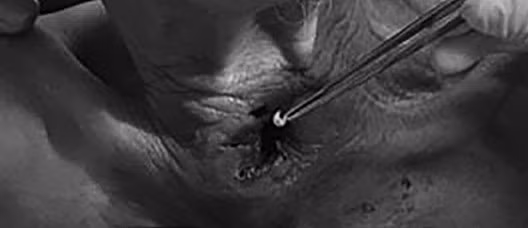

| Bác sĩ xử lý vết thương cho bệnh nhân. (Ảnh: BVCC) |

Khi tiến hành xử trí làm sạch vết thương, thay Calnuyn cho người bệnh, các bác sĩ bệnh viện nhận thấy tình trạng nhiễm trùng khá nặng và đã có giòi làm tổ. Rất bất ngờ khi các bác sĩ đã gắp được hơn 30 con giòi. Hiện người bệnh đang được theo dõi và điều trị tại khoa Tai Mũi Họng Bệnh viện.